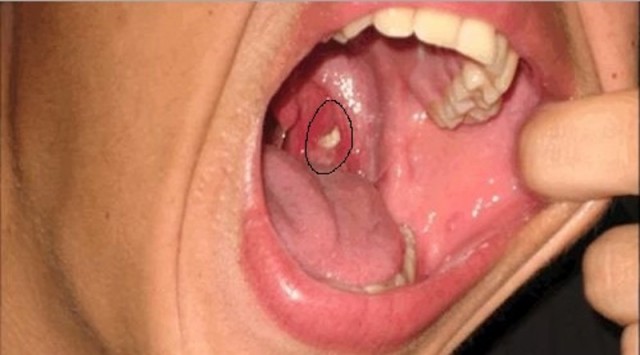

Bademcik taşları, bademcik keseleri içerisine saklanan ve görmekte zorlandığımız beyaz ya da sarı renkli partiküller.

Bademciklerde çukur şeklinde kesecikler bulunur. Ağızdaki ölü mukaza hücreleri, burundan akan mukus bademcik taşlarını oluşturur.

Süt ve süt ürünlerini tüketen insanlarda daha fazla görülmekte çünkü buradan sağlanan kalsiyum bu partiküllerin taşlaşmasında ve keseciklere sıkışmasında etkili oluyor.